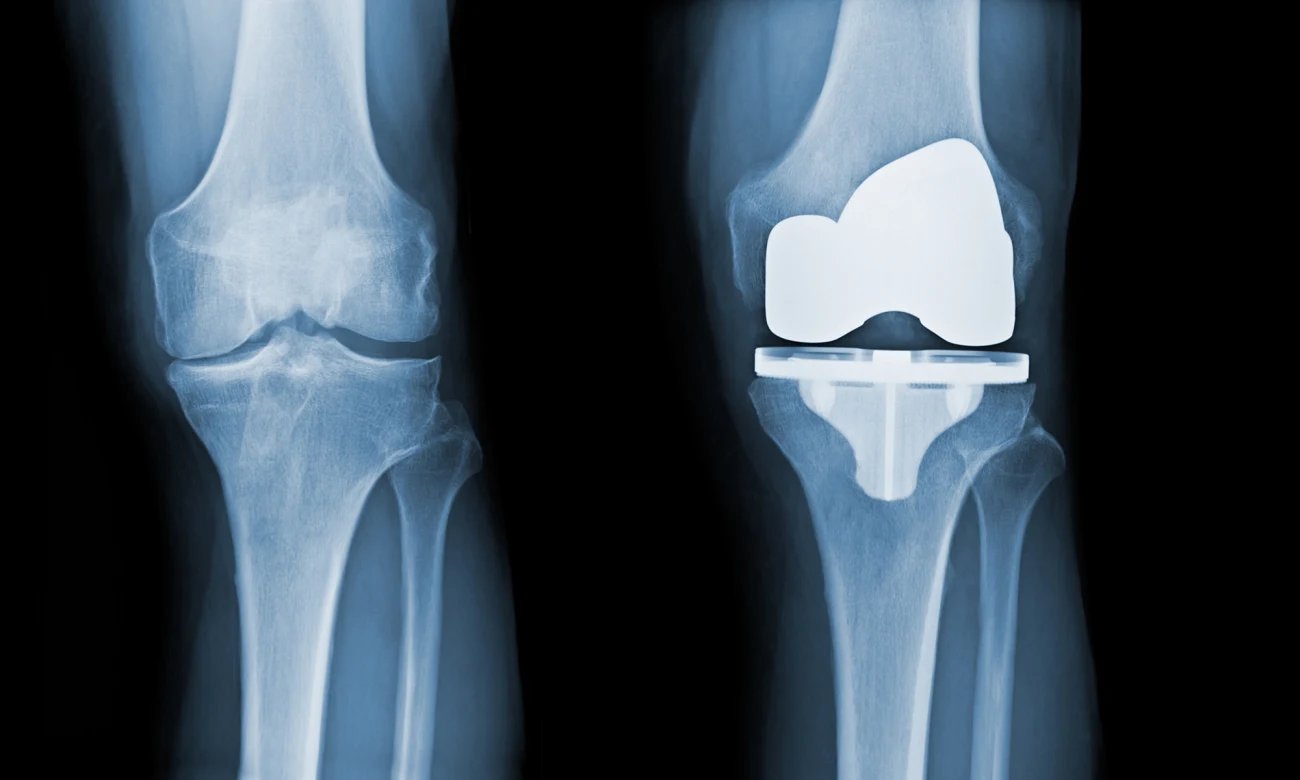

Joint Replacement

All joint replacement surgeries are performed by Dr. Ankur Rana at Summit Orthopaedic Hospital. With his surgical expertise and good physiotherapy postoperatively patients have excellent pain free range of movements in the shortest possible time.

Common joint replacement surgeries include

• 1. TOTAL HIP REPLACEMENT

• 2. TOTAL KNEE REPLACEMENT

• 3. TOTAL SHOULDER REPLACEMENT

• 4. REVERSE SHOULDER REPLACEMENT

• 5. TOTAL ELBOW REPLACEMENT

• 6. TOTAL ANKLE REPLACEMENT